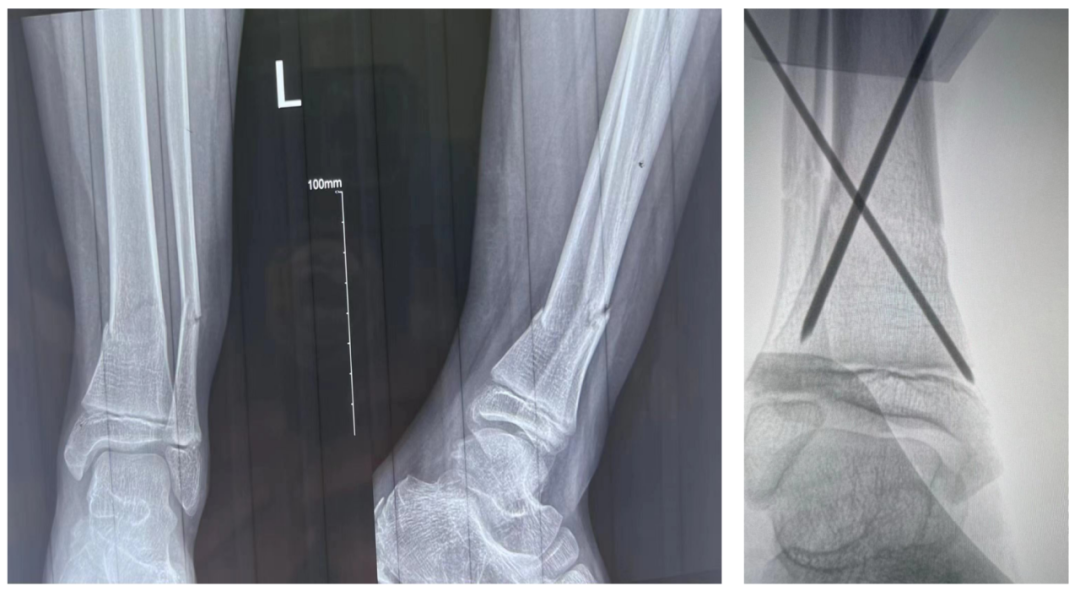

近日,一位12歲小男孩胡某因為外傷致左小腿脛腓骨骨折,為了獲得好的治療,胡媽媽帶著小胡來到了洛隆縣人民醫(yī)院骨科就診。詹志強醫(yī)師帶領(lǐng)洛隆縣人民醫(yī)院醫(yī)生洛松次登一起為患兒在全麻下給予手法復(fù)位,經(jīng)皮克氏針固定,手術(shù)僅用15分鐘就解決了患兒的病痛。

(經(jīng)皮克氏針固定治療骨折)